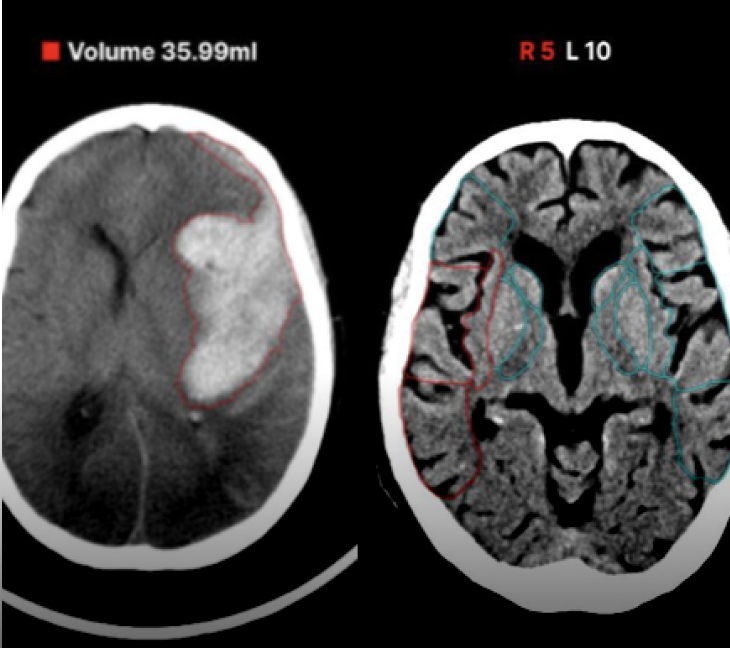

導入の相談はこちら頭部CT×高吸収/低吸収域

DoctorNET Heuron CTS

頭部非造影CT画像から、画像内の高吸収域または低吸収域を検出します

- 救急現場での読影補助として

- 頭部が専門ではない先生の補助として